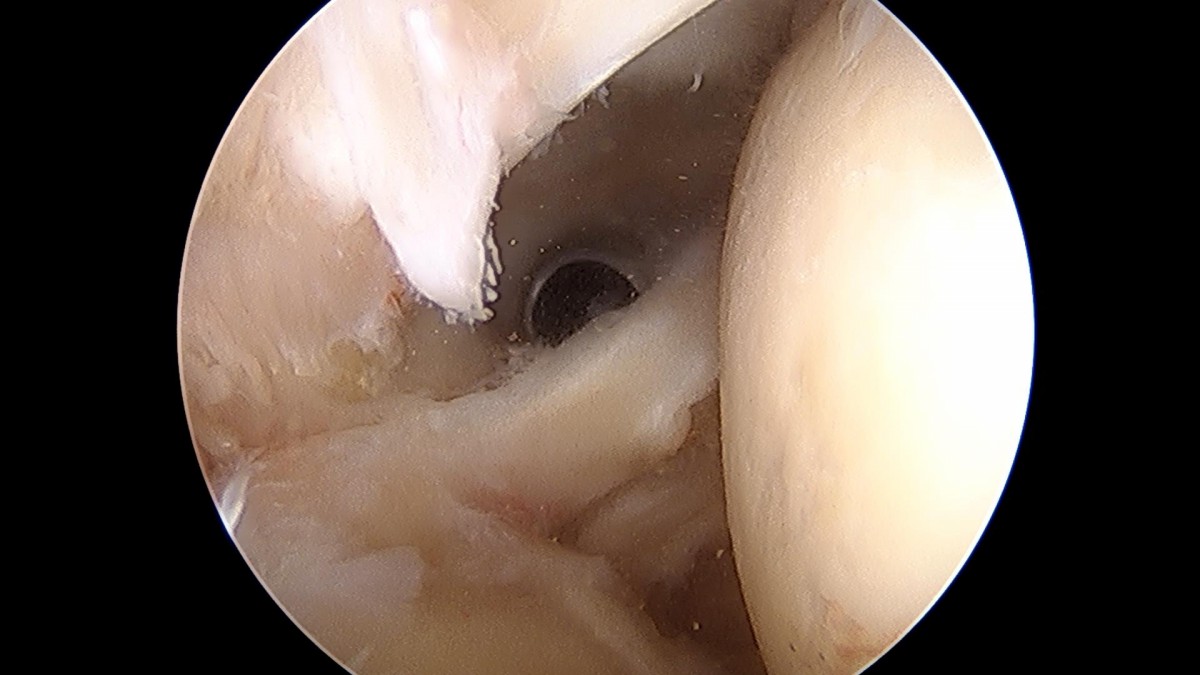

이재상원장님 어깨 회전근개 봉합술 (1305)김정O 환자

작성자 최고관리자 댓글 0건 조회 1,256회 작성일 22-02-23 14:14